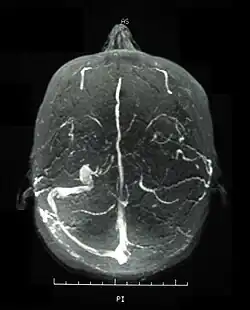

Visual acuity, or color vision loss with concurrent mucocutaneous lesions or systemic Behçet's disease symptoms should raise suspicion of optic nerve involvement in Behçet's disease and prompt a work-up for Behçet's disease if not previously diagnosed in addition to an ocular work-up. Diagnosis of Behçet's disease is based on clinical findings including oral and genital ulcers, skin lesions such as erythema nodosum, acne, or folliculitis, ocular inflammatory findings and a pathergy reaction. Inflammatory markers such ESR, and CRP may be elevated. A complete ophthalmic examination may include a slit lamp examination, optical coherence tomography to detect nerve loss, visual field examinations, fundoscopic examination to assess optic disc atrophy and retinal disease, fundoscopic angiography, and visual evoked potentials, which may demonstrate increased latency. Optic nerve enhancement may be identified on Magnetic Resonance Imaging (MRI) in some patients with acute optic neuropathy. However, a normal study does not rule out optic neuropathy. Cerebrospinal fluid (CSF) analysis may demonstrate elevated protein level with or without pleocytosis. Imaging including angiography may be indicated to identify dural venous sinus thrombosis as a cause of intracranial hypertension and optic atrophy.